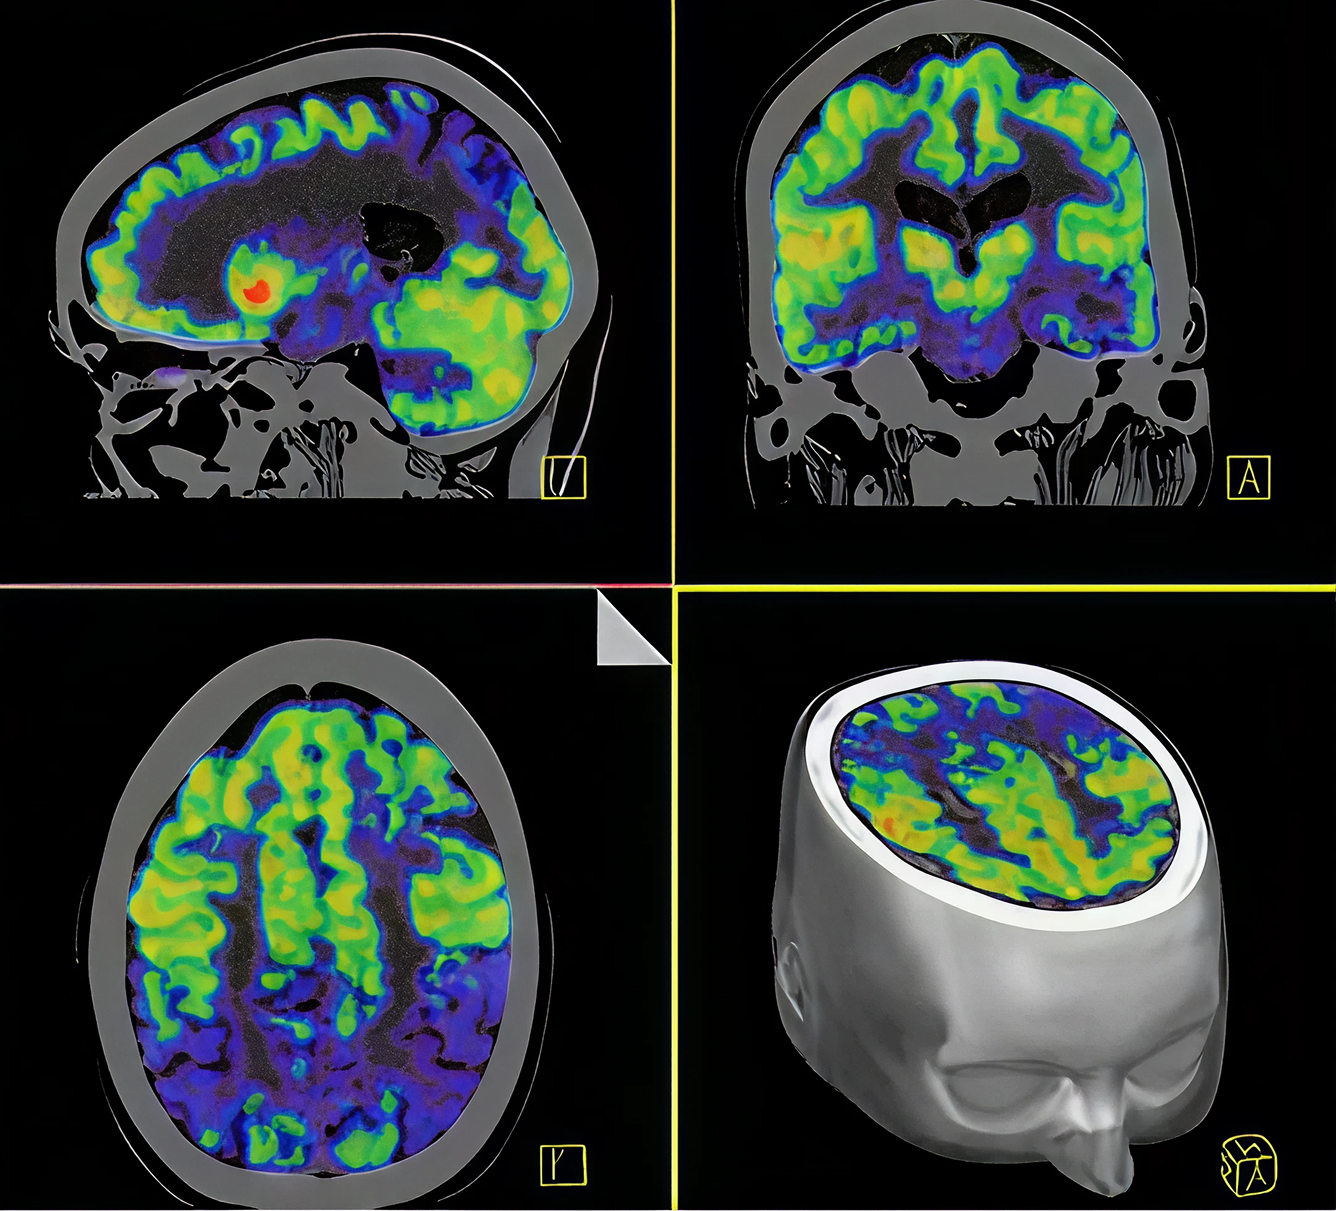

PET/CT Brain

Una tomografía de emisión de positrones de el cerebro es un análisis de imágenes tridimensionales tomadas al cerebro. En este se utiliza un marcador radioactivo para hallar algún tipo de enfermedad o daño al cerebro.

Usos y Beneficios del PET/CT del Cerebro

Un estudio PET/CT del Cerebro puede determinar como el cerebro y sus tejidos están funcionando. Otros exámenes como MRI o CT scan solo revelan la estructura cerebral.